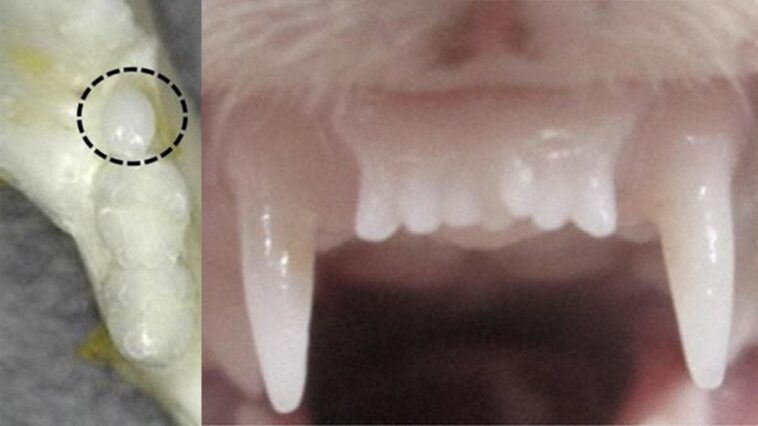

מחקר הצמחת השיניים החל ב2005 באוניברסיטת קיוטו. במהלכו התגלה גן המשפיע על צמיחת שיניים בעכברים. USAG-1 הוא נוגדן המעכב את פעולת הגן המעודד צמחית שיניים. דיכוי הנוגדן מעודד את צמיחת השיניים.

המחקר מתמקד ביצירת נוגדן מנטרל שיבלום את פעולת הנוגדן USAG-1 המעכב את פעולת הגן המעודד צמיחת שיניים.

Scientists report that an antibody for one gene — uterine sensitization associated gene-1 or USAG-1 — can stimulate tooth growth in mice suffering from tooth agenesis.